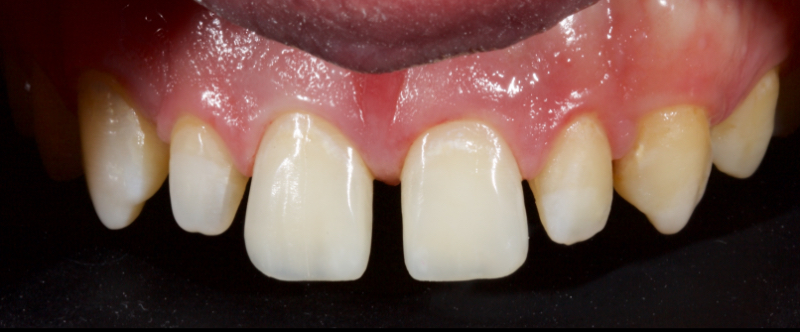

In this case, a 23-year-old male presented with Ellis Class II fractures of both central incisors (Fig. 23). He had no interest in closing his diastema or restoring the peg laterals. A treatment plan was agreed upon to restore both central incisors with direct resin.